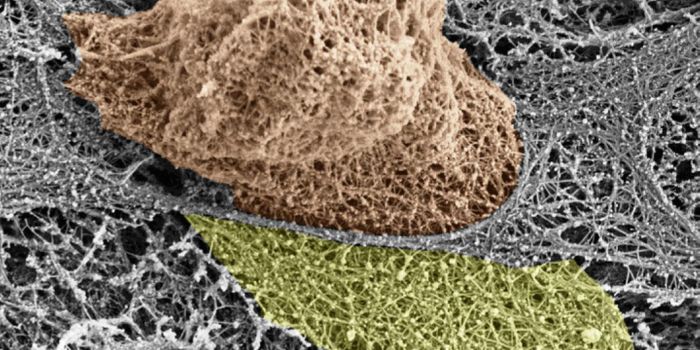

DEC 10, 2015ImmunologySuperior technology brings us novel images of cancer cells and lymphocytes this week, and now scientists can learn more ...